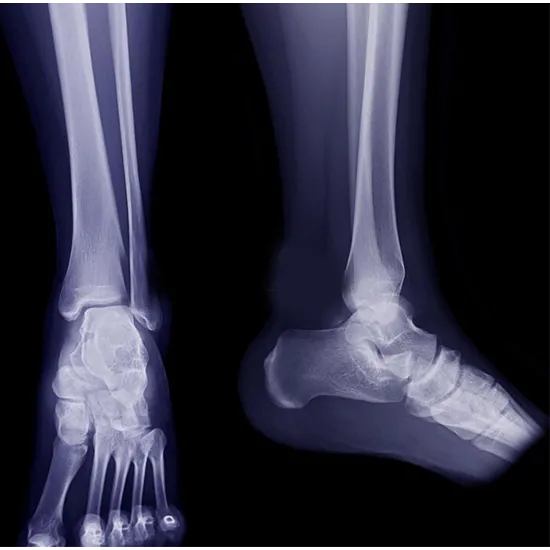

X-ray Right Heel AP & LAT View

What is an X-ray Right Heel AP & LAT View Test?

In an X-ray of the heel, a small quantity of radiation allows us to see the bone (calcaneum) and soft tissue (skin and muscles) surrounding the heel.

Why is it done?

• To diagnose fractures of the heel bone (calcaneum) and monitor the bone's healing once it has been set.

• To identify any infections, osteoporosis, malformations, or abnormal bone growth.